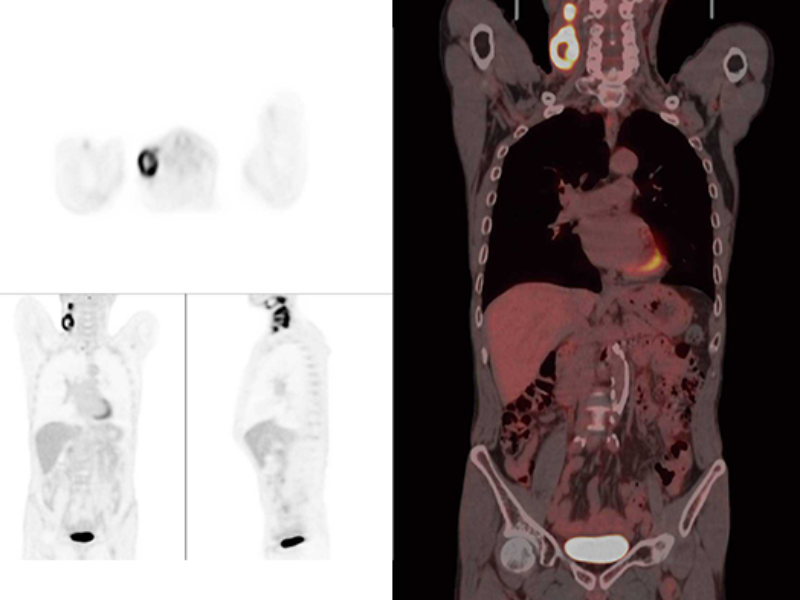

High Resolution PET

Fast Total-Body PET

Small Lesions Detectability with Gallium-68